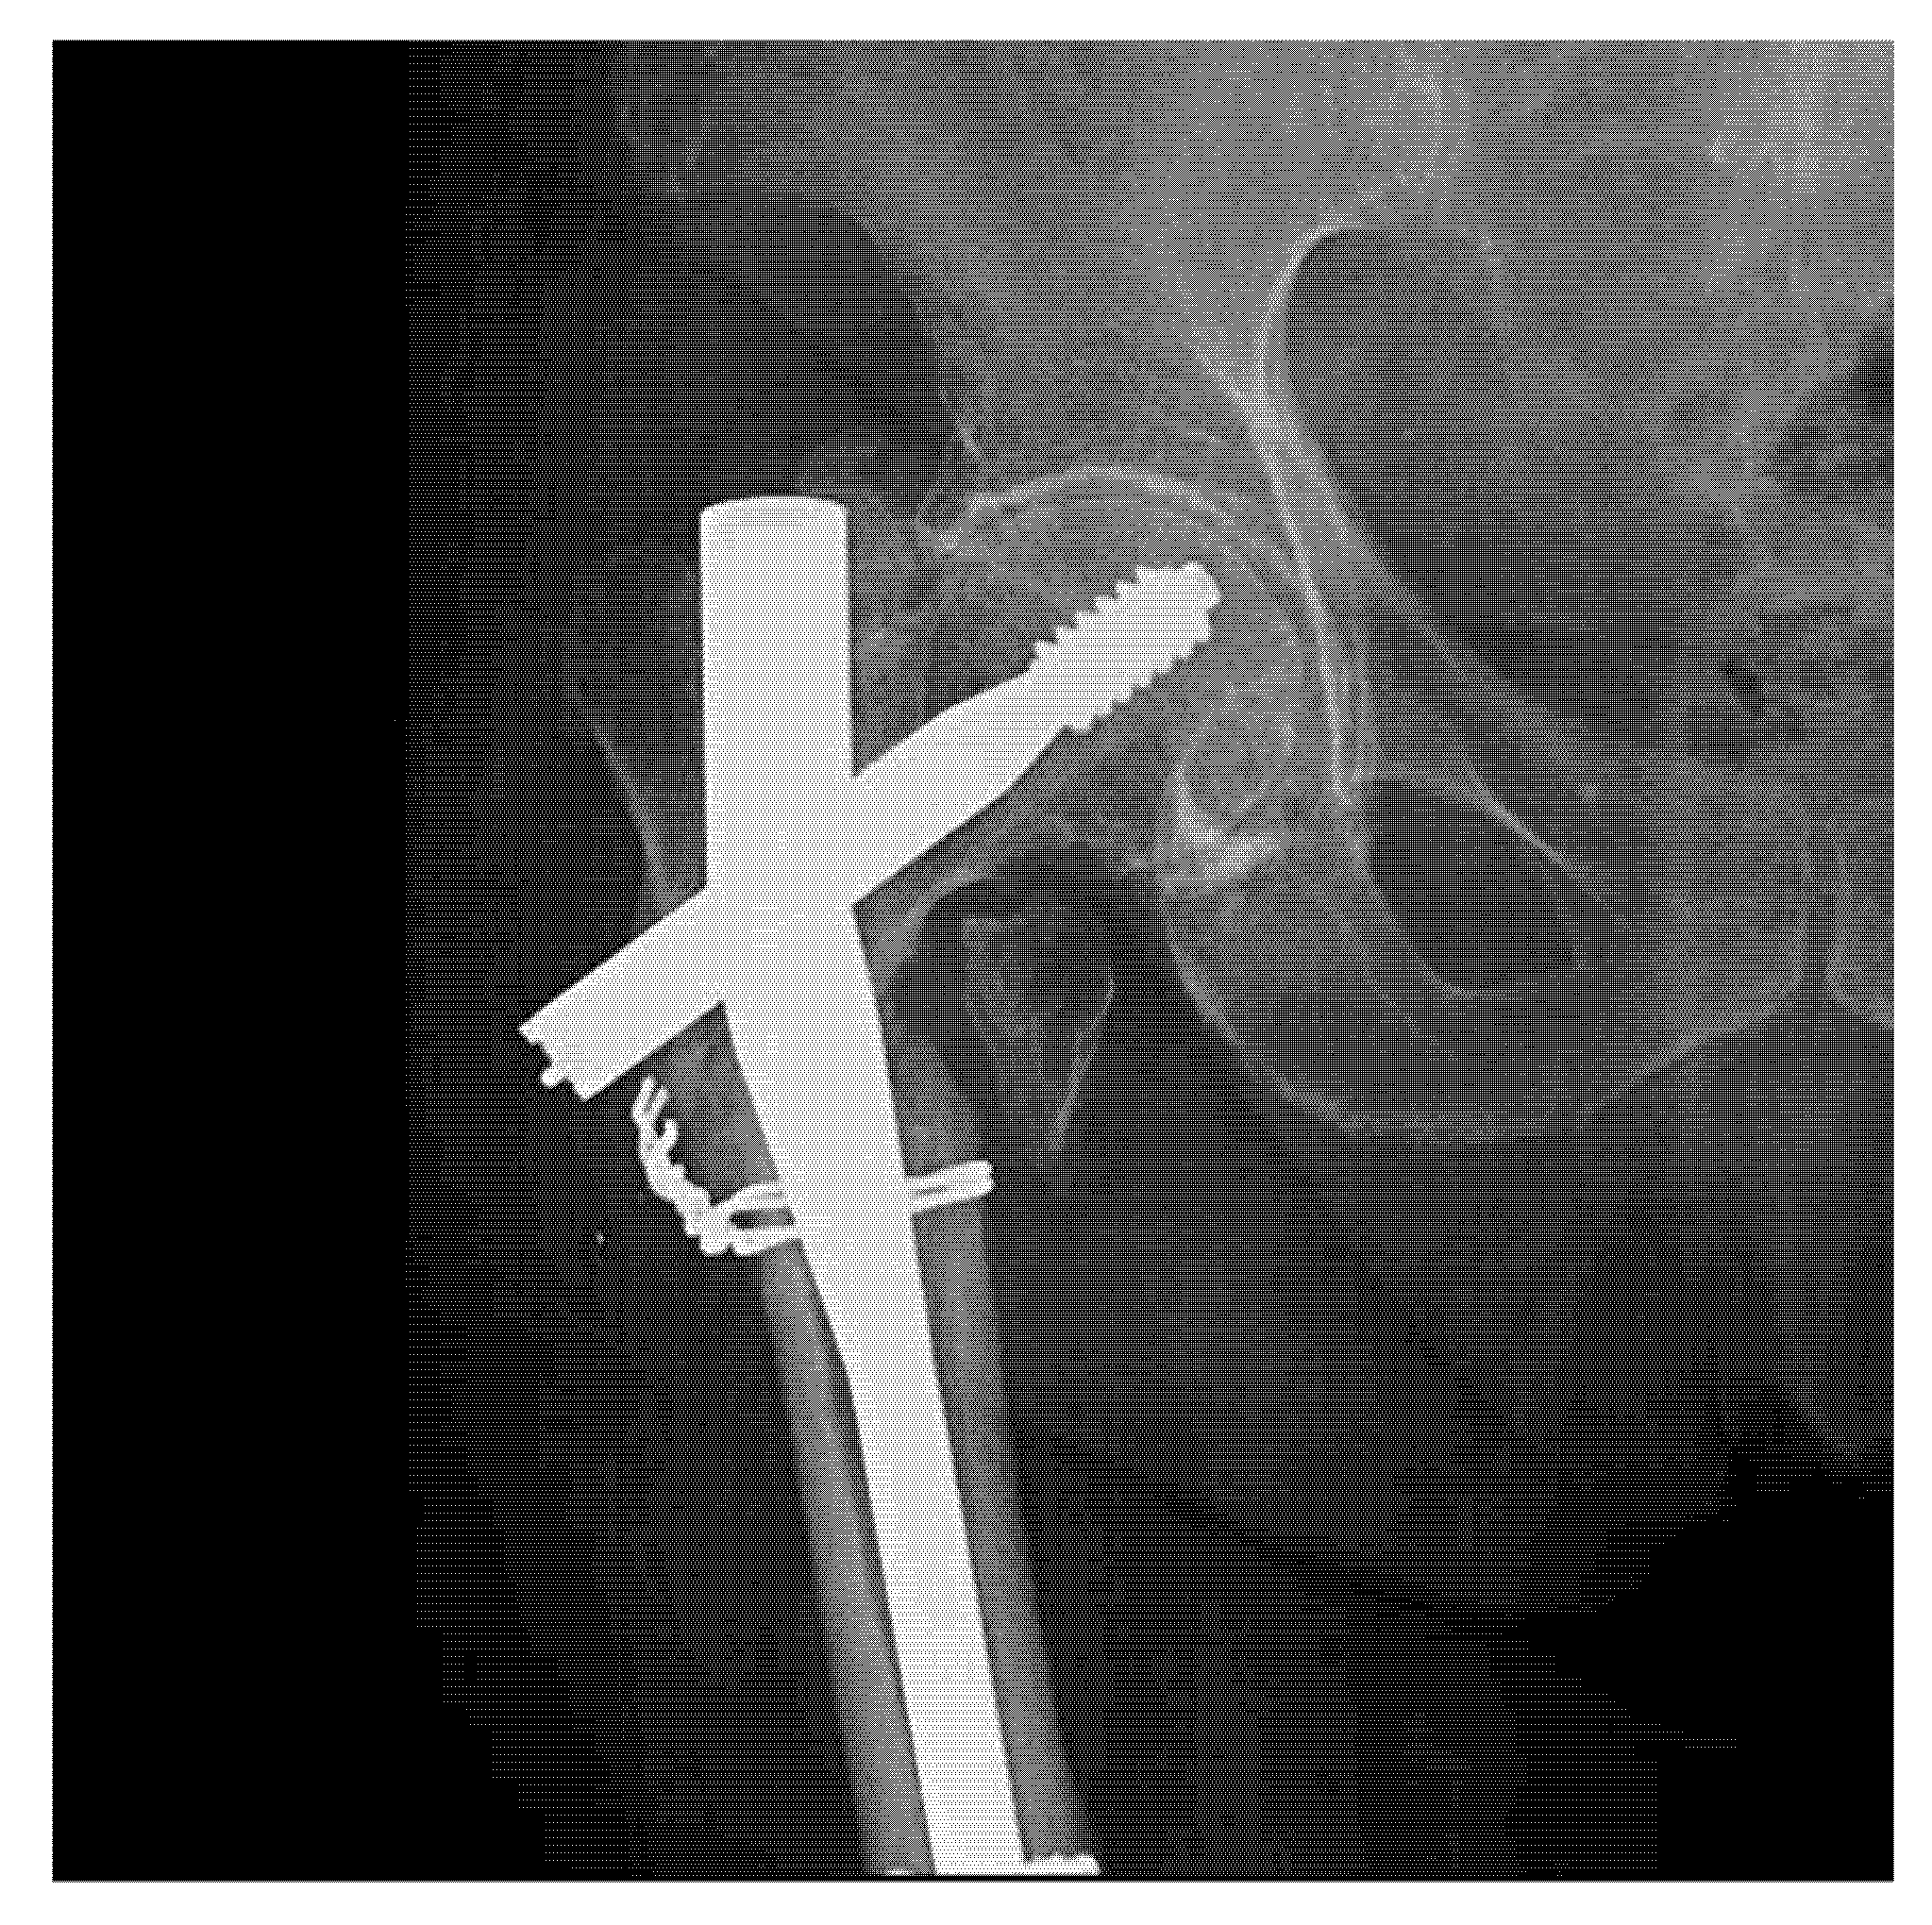

| No. | Patient Age | Fracture Location (Bone Type) | Type of Implant | Failure Causes | ||||

|---|---|---|---|---|---|---|---|---|

| External Factors (Traumatic Event) | Surgical Causes | Implant Defects | ||||||

| Inadequate Implant Size | Deficient Fracture Reduction | Materials Defects | Surface Defects | |||||

| 1 | 36 | Tibia | IMN | (+) | ||||

| 2 | 65 | Femur | IMN | (+) | (+) | |||

| 3 | 72 | Femur | GN | (+) | ||||

| 4 | 26 | Humerus | PS | (+) | ||||

| 5 | 44 | Tibia | IMN | (+) | (+) | (+) | (+) | |

| 6 | 31 | Tibia | PS | (+) | (+) | (+) | ||

| 7 | 71 | Femur | GN | (+) | ||||

| 8 | 67 | Femur | DHS | (+) | (+) | |||

| 9 | 39 | Humerus | IMN | (+) | (+) | |||

| 10 | 78 | Femur | DHS | (+) | ||||

| 11 | 46 | Tibia | IMN | (+) | (+) | (+) | ||

| 12 | 42 | Humerus | PS | (+) | (+) | |||

| 13 | 69 | Femur | DHS | (+) | ||||

| 14 | 18 | Humerus | IMN | (+) | ||||

| 15 | 68 | Femur | DHS | |||||

| 16 | 32 | Humerus | PS | (+) | (+) | |||

| 17 | 74 | Femur | GN | (+) | ||||

| 18 | 59 | Femur | DHS | (+) | ||||

| 19 | 46 | Humerus | IMN | (+) | (+) | |||

| 20 | 55 | Tibia | IMN | (+) | ||||

| 21 | 69 | Femur | DHS | (+) | ||||

| IMN=Intramedullary Nail; GN=Gamma Nail; DHS=Dynamic Hip Screw; PS=Plate-Screw System | ||||||||